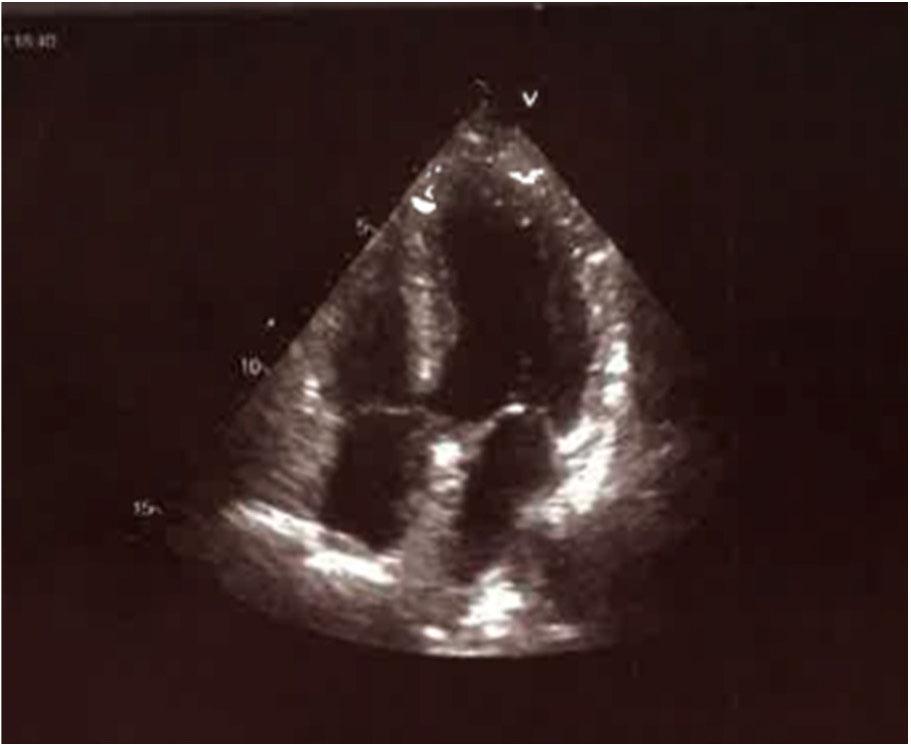

However, the coronary arteries appeared normal on the coronary angiogram (Figure 2), with no evidence of any atherosclerosis or stenosis. An echocardiographic examination performed after 3 days shows reference LV dimensions, without previously observed systolic dysfunction, with a preserved EF of 55%, without segmental outbursts. Ballooning of the apex is not observed.

Transthoracic echocardiographic apical four-chamber view in systole showing ballooning of the apical segments 3 days later

The diagnosis of Takotsubo myopathy was made based on the complete reversibility of the described echocardiographic changes. It was presented with an electrocardiographic image of an acute STEMI infarction, with verified markers of myocardial necrosis, including high-sensitivity troponin, clear contractility outbursts in the echocardiogram, regular coronary findings, and full reversibility of the described electrocardiographic and echocardiographic changes (Fig. 2)